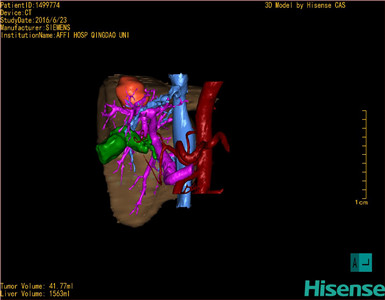

通过调节窗宽窗位调整CT序号,对肿瘤,肝实质,胆囊,下腔静脉,肿瘤,肝动脉、门静脉及肝静脉等进行三维重建;系统自动计算肿瘤体积和肝脏体积。

模拟手术操作,自动计算切除肿瘤体积。肝脏体积为1536ml,肿瘤体积为41.77ml,肿瘤体积为肝脏体积2.7%,通过比60-70岁正常肝脏体积为1262.7±284.31ml,通过术前模拟手术,精准判断切除后剩余肝脏体积能耐受,避免肝衰竭发生。

术前三维重建:

重建图片